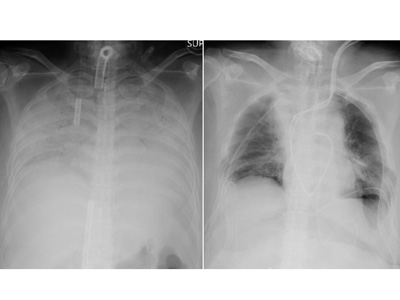

Μία γυναίκα στην Ιαπωνία της οποίας οι πνεύμονες είχαν πάθει σοβαρή ζημιά από τον κοροναϊό, γίνεται σύμφωνα με τους θεράποντες ιατρούς ο πρώτος ασθενής κόσμο στον οποίο γίνεται μεταμόσχευση από ζωντανό δότη.

Όπως αναφέρει σε ανακοίνωσή του το Πανεπιστημιακό Νοσοκομείο του Κιότο η γυναίκα υποβλήθηκε σε εγχείρηση 11 ωρών από ιατρική ομάδα 30 ατόμων την Τετάρτη για μεταμόσχευση πνευμονικού ιστού από τον σύζυγο και τον γιο της.

Ο κοροναϊός είναι γνωστό ότι προκαλεί σοβαρή πνευμονική βλάβη σε ορισμένους ασθενείς και άνθρωποι σε όλο τον κόσμο – συμπεριλαμβανομένων των Ηνωμένων Πολιτειών – έχουν λάβει μεταμοσχεύσεις πνευμόνων ως μέρος της ανάνηψής τους από την ασθένεια.

Ωστόσο, το νοσοκομείο του Κιότο είπε ότι αυτή η περίπτωση ήταν η πρώτη στον κόσμο στην οποία μεταμοσχεύθηκε ιστός πνεύμονα από ζωντανούς δότες σε ασθενή Covid-19, όπως μεταδίδει το CNN.

Σύμφωνα με το Πανεπιστημιακό Νοσοκομείο του Κιότο, η ασθενής της οποίας το όνομα δεν έχει γίνει γνωστό, με καταγωγή από την επαρχία Κανσάι, νόσησε από κοροναϊό στα τέλη του 2020 και πέρασε τους επόμενους μήνες σε μηχανική υποστήριξη.

Ο κοροναΐός είχε κάνει τόσο μεγάλη ζημιά και στους δύο πνεύμονες που χρειαζόταν άμεσα μεταμόσχευση προκειμένου να ζήσει.

Ο σύζυγος και ο υιός της γυναίκας προσφέρθηκαν να δωρίσουν μέρη των πνευμόνων τους. Οι μεταμοσχεύσεις από εγκεφαλικά νεκρούς δότες εξακολουθούν να είναι σπάνιες στην Ιαπωνία και οι ζώντες δότες θεωρούνται καλύτερη επιλογή, σύμφωνα με τη δήλωση του νοσοκομείου.

Η υγεία τόσο του συζύγου όσο και του γιού είναι σταθερή ενώ η μητέρα νοσηλεύεται στην μονάδα εντατικής θεραπείας και αναμένεται να πάρει εξιτήριο σε περίπου δύο μήνες.